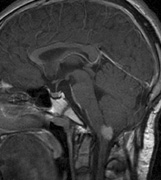

CNS hemangiomas are the most common tumor of VHL, affecting 60% to 80%, with a predilection for the cerebellum and spinal chord. An enlarging cystic component is a frequent finding in symptomatic tumors. Patients typically present in their early 30s; headaches or neck pain in affected individuals should not be ignored.172,173 On microscopy, CNS hemangiomas resemble retinal capillary hemangiomas. Their malignant potential is low.174 The treatment is surgical (Fig. 17, A and B).13

Fig. 17. Images from a 13-year-old boy with Von Hippel-Lindau syndrome. (a) Coronal postcontrast T1-weighted imaging reveals a cystic lesion with an enhancing nodule at the pial surface typical of a hemangioblastoma. (b) A second solid enhancing hemangioblastoma is seen at the craniocervial junction on a sagittal postcontrast T1-weighted image. (c) Associated cystic lesions (arrows) are seen within the pancreas.

Pancreatic lesions may be nonsecretory (most commonly cysts or cystadenomas) or secretory (islet cell tumor).179 In one study of 52 patients, 56% (29 patients) were found to have pancreatic lesions. The majority (19 of 29) had cystic changes only (Fig. 17C). Pancreatic lesions were the only abdominal manifestation of disease in 6 of 52 patients.180 In a separate study, pancreatic cysts did not show significant progression on follow-up examinations over an average period of 5 years.181 Like pancreatic cysts, islet cell tumors appear to be frequently asymptomatic.182